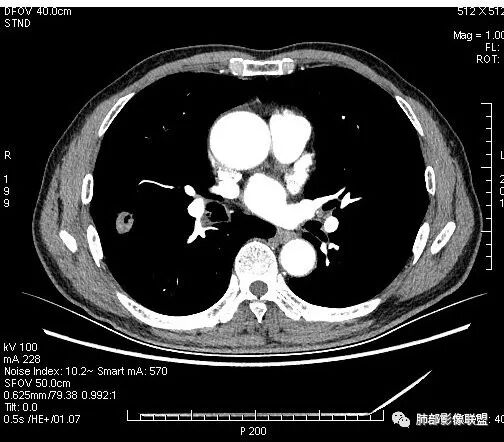

晨读:男,67岁,体检发现右肺结节。近圆形,支气管及伴行血管进入结节,进入结节后支气管堵塞,血管走形尚自然,结节内血管边缘凹凸不平。远端边缘见毛刺(软毛刺?)及分叶。见胸膜牵拉。实变中见空洞。整体膨胀感不明显。考虑炎性肉芽肿可能,隐球菌病可能性大。注意鉴别鳞癌、结核。

虽然良恶性征象都有,但是这个病灶增强后坏死比较明显,如果是恶性:腺癌这样大小的结节坏死很少见,只有低分化腺癌可以坏死,但是低分化腺癌这种大小一般会有周围转移表现(叶间胸膜结节,癌淋或者淋巴结明显肿大),如果是鳞癌,收缩力,坏死情况以及没有支气管截断都不太支持,而且结节远端有几个小结节样改变,大家可能认为是血管,但我觉得应该是卫星灶。所以觉得隐球可能较大。壁胸膜的牵拉线也没有引起胸膜凹陷,比较纤细,至于病理中的丝状物不一定是真菌菌丝。

4.病灶轻到中度强化。病灶内血管走行较完好,病灶旁血管局部显示粗大。

5.支气管关系不确定。

病灶内“旁若无人”的血管走形也让人难以理解。而该疑问也存在于结核病灶的辨析当中。